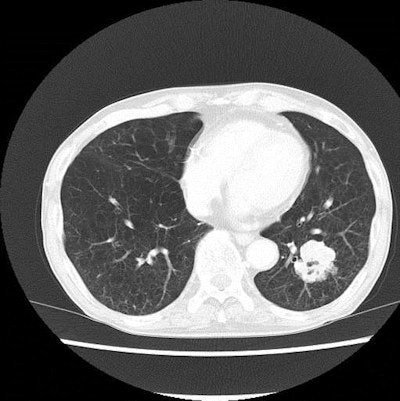

Radiation dose can be lowered by carefully following proper techniques such as correct patient positioning, appropriate scan length, and shielding the radiosensitive organs. For chest CT, shielding the mammary glands and the thyroid gland are applicable options. However, shielding could be harmful because of noise and artifacts, Kubo and colleagues noted. Scan parameters such as tube current and peak energy also can be adjusted for dose reduction. These too often come at a cost in image quality, though. Auxiliary measures that indirectly contribute to radiation dose reduction include alternative reconstruction algorithms or image filters. When the techniques are used with parameter modification to aid in radiation dose reduction, image quality is ameliorated.